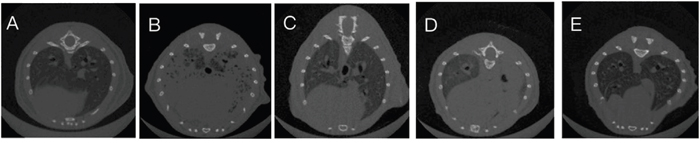

CT scans of the mice lungs of all treatment groups at 48 h after LPS administration were generated. The results showed that compared with the LPS+PBS group, mice in LPS+hUC-MSCs, LPS+FTY720, and LPS+hUC-MSCs+FTY720 groups showed clearly attenuated inflammation in the lungs after LPS challenge (Figure 1).

Figure 1: CT scans of lung tissues at 48 h after LPS challenge. (A) Control, (B) LPS+PBS, (C) LPS+hUC-MSCs, (D) LPS+FTY720, (E) LPS+ hUC-MSCs+ FTY720.